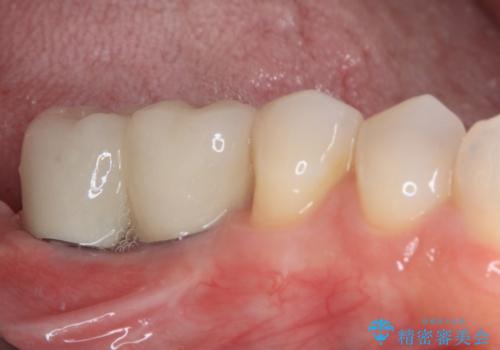

不正咬合で抜歯となった奥歯 インプラントによる咬合回復

長年の咬合により、周囲の奥歯がすり減っているため、よりインプラントが長い期間安定するよう、睡眠時にはマウスピースを装着することを強く推奨しています。